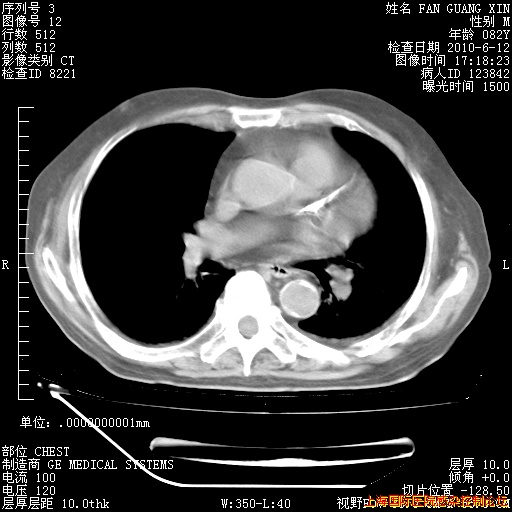

6月12日纵膈窗

整整相隔30天的肺部CT好像有所好转啊。甲强龙减量第3天,需要观察体温。